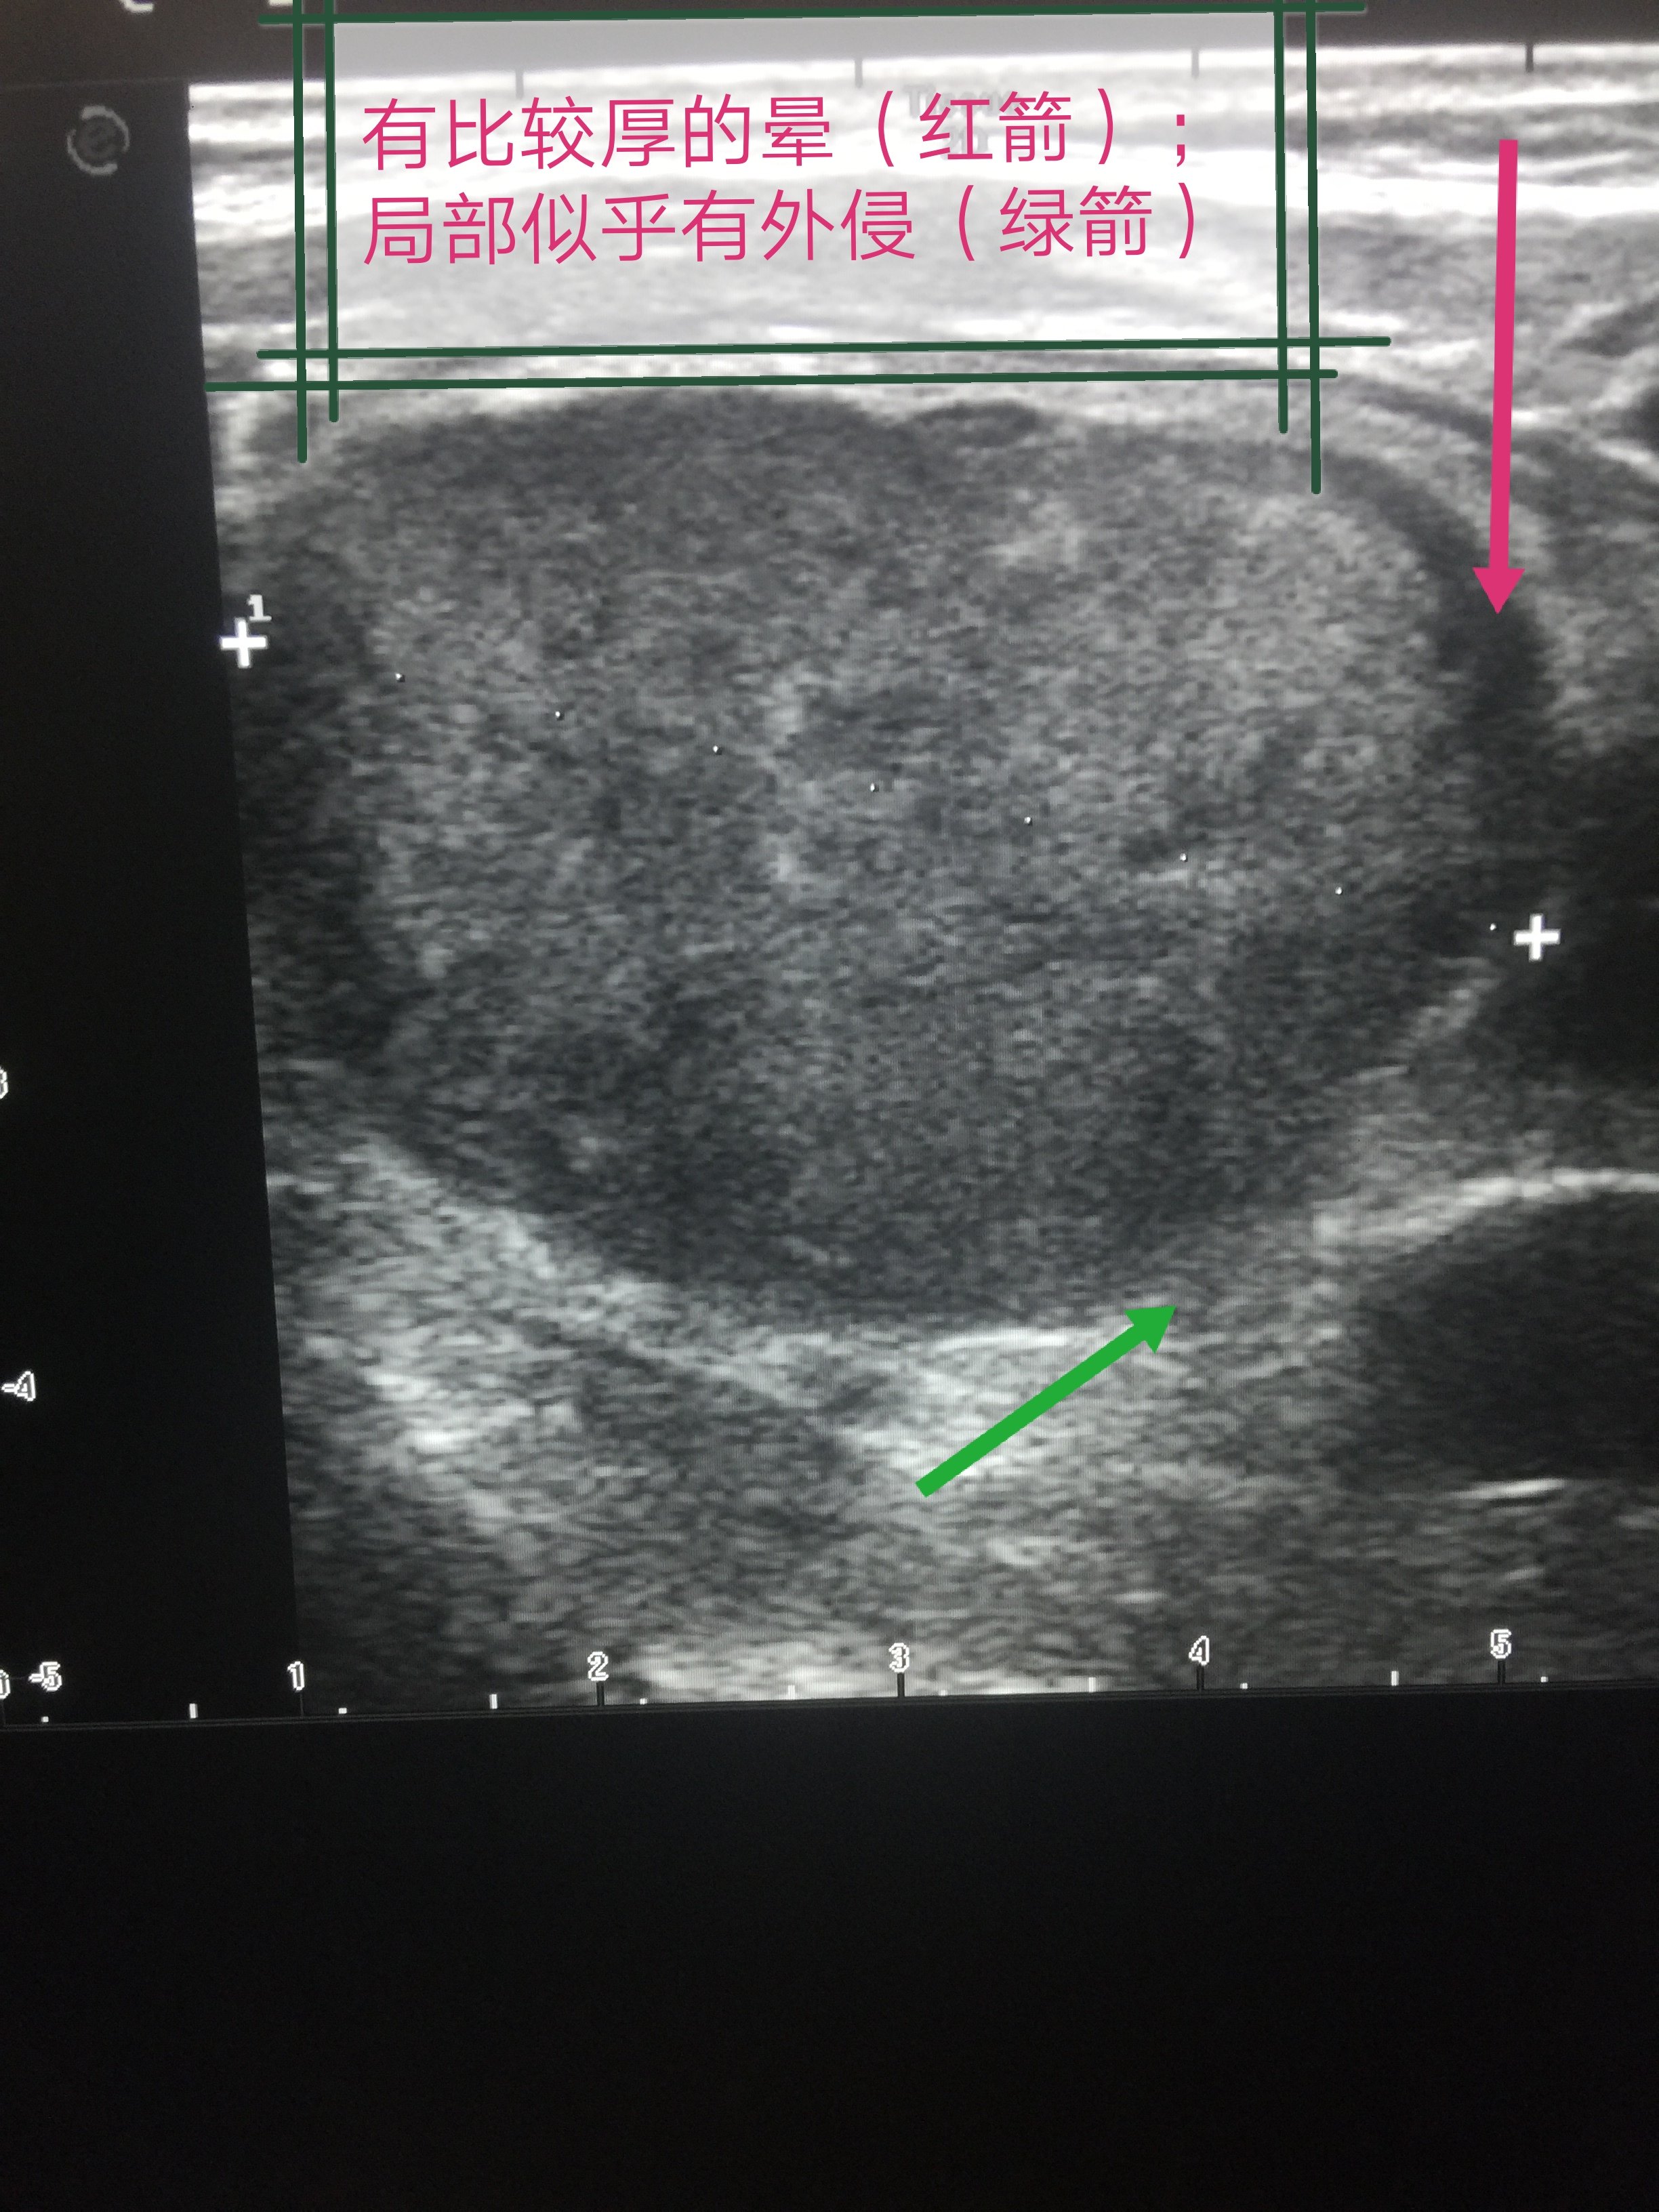

超声诊断甲状腺乳头状癌累及包膜1例原创

图片尺寸1080x1440